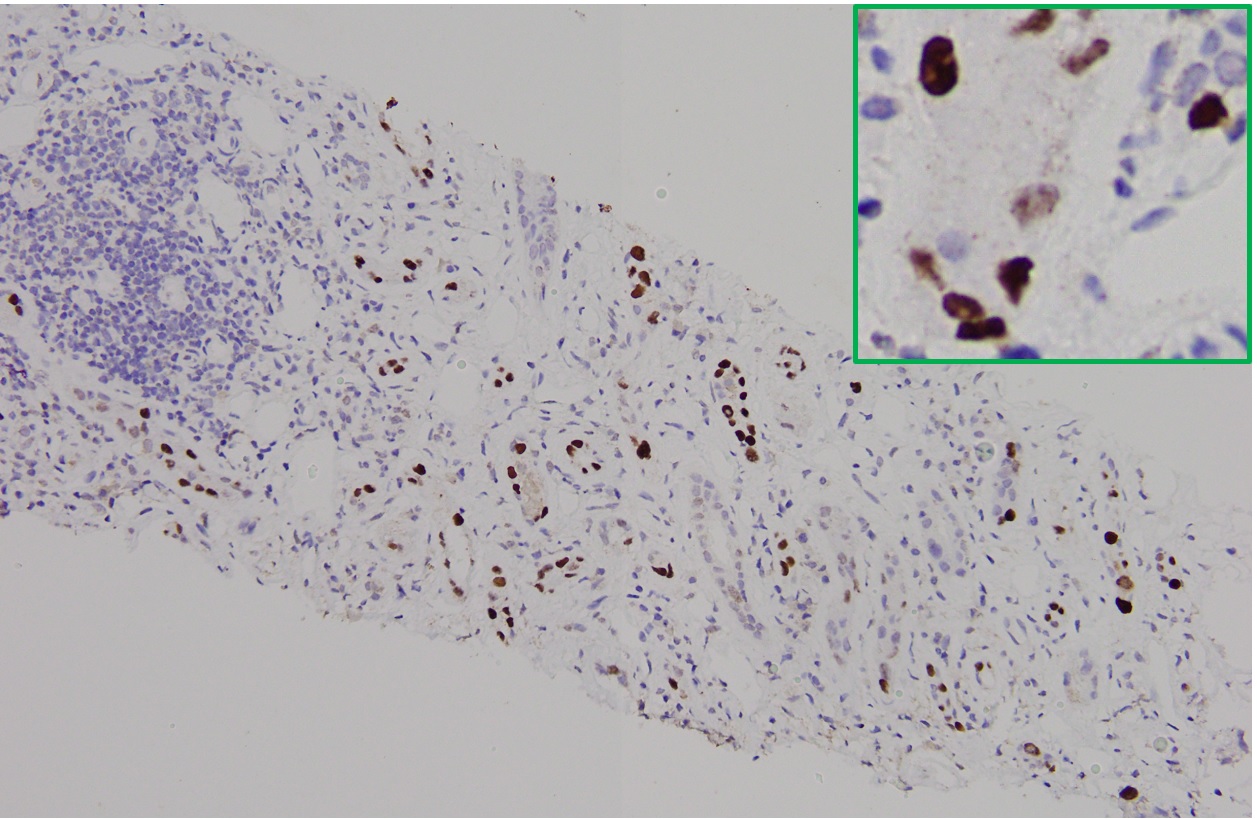

It is not always easy of straightforward to distinguish BK nephropathy from acute rejection, and very difficult to diagnose a coexisting lesion including both of them. T cell-mediated rejection shares similar histopathologic features with BK nephropathy, such as focal and brisk interstitial inflammation and tubulitis (shown in Fig. 1). However, typical viral cytopathic changes are more common in BK nephropathy, such as nuclear enlargement and intranuclear infusion (Fig. 2, yellow arrow) and features resenbling so called "decoy cells" in urine cytology (Fig. 2, red arrow). SV-40 large T antigen staining with IHC confirms a diagnosis of polyomavirus infection (shown in Fig. 3), but can't differentiate BK from JC virus. Interestingly, some patients with BK nephropathy shows C4d deposits in the tubular basement membrane (Fig. 4), but not the typical pattern of peritubular linear C4d stain for antibody-mediate rejection.